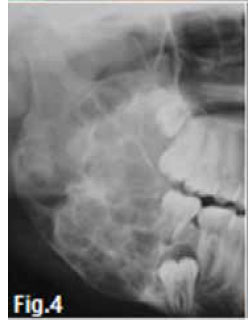

Figure 1 & 2 shows an aggressive lesion in a 14 year old male patient. The pantomograph show the lesion extending from the 36 to the 46. Expansion of the cortex and divergence of the roots is discernible. A histological diagnosis of a Central giant cell granuloma (CGCG) of the bone was made. The original term of CGCG was coined by Jaffe in 1953, when he suggested that this lesion should be distinguished from the Central giant cell tumour (GCT) of bone. Jaffe believed that the CGCG is a reactive lesion, whereas the CGT is a neoplasm. Central giant cell granuloma of the jaws is considered to be a fairly common benign reactive lesion. It is characterized by the presence of numerous multinucleated giant cells. The CGCG most commonly affects young people and over 50% of cases occur in the first two decades of life. The average age of occurrence is 21 years, with a range of 3 to 68 years. Females are affected slightly more than males. The mandible is affected in the majority of cases, with the anterior segments being affected more often than the posterior. Radiographically the lesion is essentially radiolucent, often with a multilocular, soap bubble appearance (Fig.3). A rather marked expansion with thinning of the cortical plates is a characteristic finding (Fig.4). The tumour usually destroys the lamina dura and causes displacement of the teeth (Figs.2 & 3). It may lie in intimate contact with the teeth, causing very few changes; in other areas it may cause extensive root resorption. This root resorption is usually irregular and leaves a ragged surface in contrast to the smooth resorption seen in association with cysts. According to Langlais et al.(1994), CGCG's can present with an aggressive or non-aggressive behaviour. The basis for this division consisted of histologic, clinical and radiological factors. The radiological features of the aggressive type include resorption of adjacent root apices, perforation of the expanded cortex and a diameter exceeding 2cm; nonaggressive lesions are characterized by the absence of root resorption, intact cortices and a diameter smaller than 2cm. A peripheral variant of this lesion occurs in the gingiva and produces an epulis-like soft tissue mass in the gingival region. In a edentulous area it may result in a nodule or swelling on the alveolar ridge and may present radiologically with a typical "peripheral cuffing" (red arrows, Fig.5). The CGCG are known to recur, and recurrence is a feature of the aggressive type and may require curettage plus peripheral ostectomy A histological diagnosis of CGCG must always be followed by a workup for the possibility of the presence of a "Brown" tumour of hyperparathyroidism.